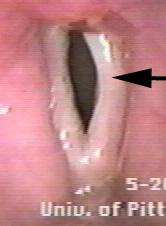

(三)双侧不完全性麻痹:少见,多因甲状腺手术或喉外伤所致。两侧声带均不能外展而相互近于中线,声门呈小裂隙状,患者平静时可无症状,但在体力活动时常感呼吸困难。一旦有上呼吸道感染,可出现严重呼吸困难。